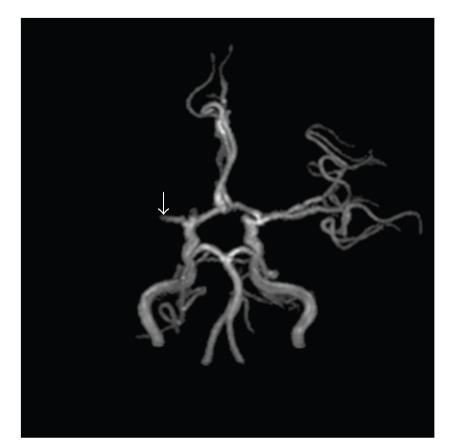

Background. Although thrombolytic therapy has been shown to be beneficial to stroke patients, the effectiveness of intravenous thrombolysis in ischemic stroke patients with ventricle myxoma is unknown. Case Description. A 22-year-old woman with left hemiplegia was sent to the emergency department at a teaching hospital. The magnetic resonance angiography showed occlusion of the right middle cerebral artery, and the echocardiography showed a mass in the left ventricle. Intravenous recombined tissue plasminogen activator (rt-PA) was administrated, and the postthrombolysis transcranial Doppler exam showed that her right middle cerebral artery was circulative. The patient's condition improved gradually, and no complication was observed up to 16 months of follow-up. Conclusion. Intravenous rt-PA is a reasonable treatment for stroke patients with ventricle myxoma.

背景。尽管溶栓治疗已被证明对中风患者有益,但静脉溶栓治疗在患有心室黏液瘤的缺血性中风患者中的有效性尚不清楚。病例描述。一名22岁左侧偏瘫女性被送往一家教学医院的急诊科。磁共振血管造影显示右大脑中动脉闭塞,超声心动图显示左心室有肿物。给予静脉注射重组组织型纤溶酶原激活剂(rt-PA),溶栓后经颅多普勒检查显示其右大脑中动脉有血流。患者病情逐渐改善,随访16个月未观察到并发症。结论。静脉注射rt-PA是患有心室黏液瘤的中风患者的合理治疗方法。